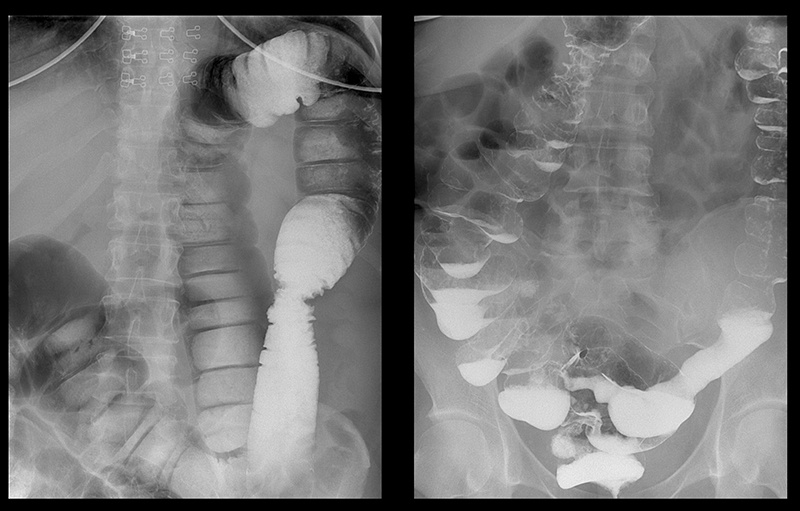

Подивіться знімки органів людей, у яких усе почалося з неприємного запаху з рота, закрепів та печії, а закінчилося доповіддю патологоанатома.

‘’Рентгенографія калового каміння в товстій кишці’’

‘’Стадії раку прямої кишки які формуються протягом 1-2 років’’